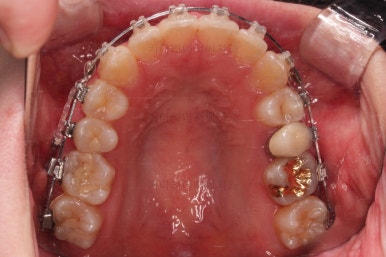

부산비대칭교정 마무리 때의 입안의 모습입니다.

가지런한 느낌은 좋지만 정중선 당연히 약간 안맞고요.

폭도 100%는 안맞아서 어금니쪽이 약간 애매한 교합이기도 했습니다.

하지만 이정도의 비대칭 상황에서 이정도의 교합은 교정만으로 할 수 있는 베스트가 아닌가 생각됩니다.

전후 비교 사진인데요.

입매가 비발치임에도 불구하고 매우 좋아졌고요.

치열과 교합도 매우 좋아졌습니다.

웃을 때 보이는 치열의 기울기도 좋아졌고요.

입을 다물었을 때 입술의 기울기도 처음보다는 좋아졌는데 앞서 말씀드린대로 뼈의 위치가 좋아졌다거나 뼈의 형태가 개선되어서 그런게 아니고요. 치열이 가지런해지고 입이 들어감으로서 입술이 다물어지는 편안한 정도가 바뀌면서 마치 입술의 비대칭까지 좋아진 듯한 착시효과가 생기는 것입니다.

비대칭은 여전히 비대칭입니다.

다만, 그 안에서 최대한 양호한 교합과 모양을 찾아가는 것이 이번 부산비대칭교정 치료의 목표였고, 그런 목표에서는 상당히 만족스럽게 치료가 끝났다고 판단됩니다.